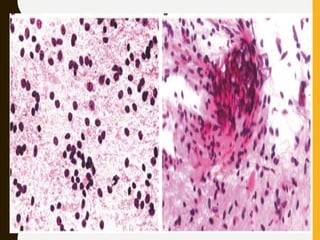

Reactive gliosis: (a) Clump of evenly spaced reactive astrocytes

and some inflammatory cells (Smear, Romanowsky). (b) Two

stellate-shaped reactive astrocytes with tapering cytoplasmic

processes and mild nuclear enlargement

Binucleation (mirror nuclei) and tapering processes radiating

out from all around the cell suggest it is nonneoplastic.